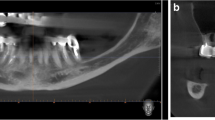

First, the head position on CBCT was corrected from the coronal, sagittal and horizontal planes for each patient by using the Simplant software. Curved sections were then reconstructed along the line connecting the midpoint of the mandibular alveolar ridge. The distances from the mandibular canal to the buccal cortex, lingual cortex and alveolar crest were measured in a vertical cross-section at the center of the mandibular second molar space on the curved surface (Fig. 1A). If multiple consecutive teeth in the mandible were missing, the vertical cross-section at the midpoint of the mesial-apical line of the maxillary second molar was taken for measurement. All patients were virtually implanted with 4.1 × 10-mm (Bone Level Tapered Roxolid SLA, Straumann, Switzerland) to analyze the feasibility of the simulated trans-IAN implantation and to further screen out the patients in whom the ultrashort implant could not be vertically implanted for the feasibility simulation. A safe distance of at least 1.5 mm from the mandibular canal and the buccal bone plate was maintained and the minimum and maximum buccal-lingual inclination angles of the implant were measured (Fig. 1B, C).

Cone beam computed tomography. A Measurement of the distance from the mandibular nerve canal (red circle) to the buccal cortex (blue arrow), the lingual cortex (green arrow) and the alveolar crest (yellow arrow). B and C Measurement of the minimum (B) and maximum (C) angles of buccal-lingual inclination of the virtual implant